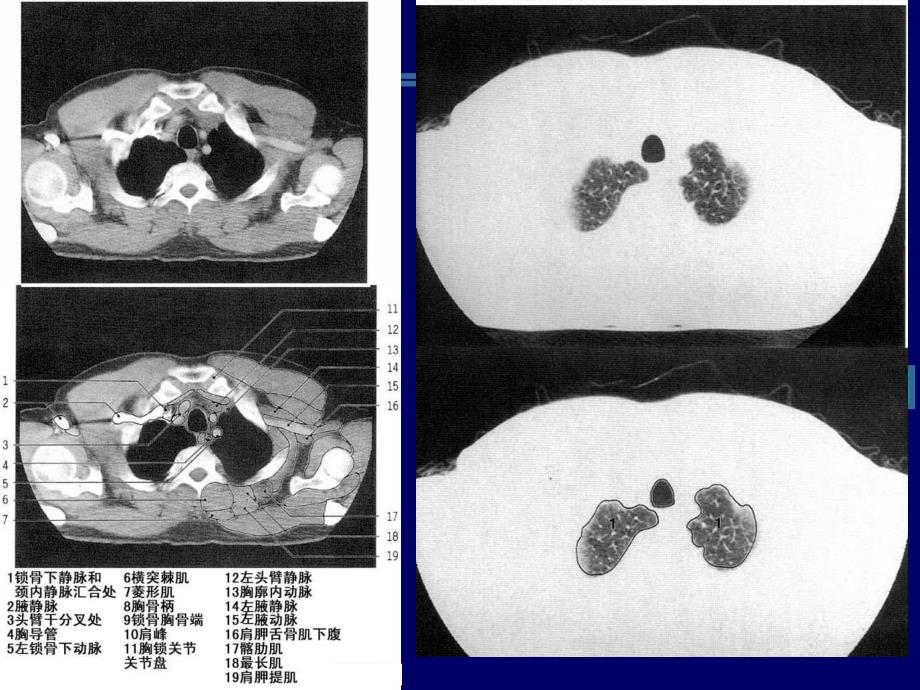

CT胸部解剖